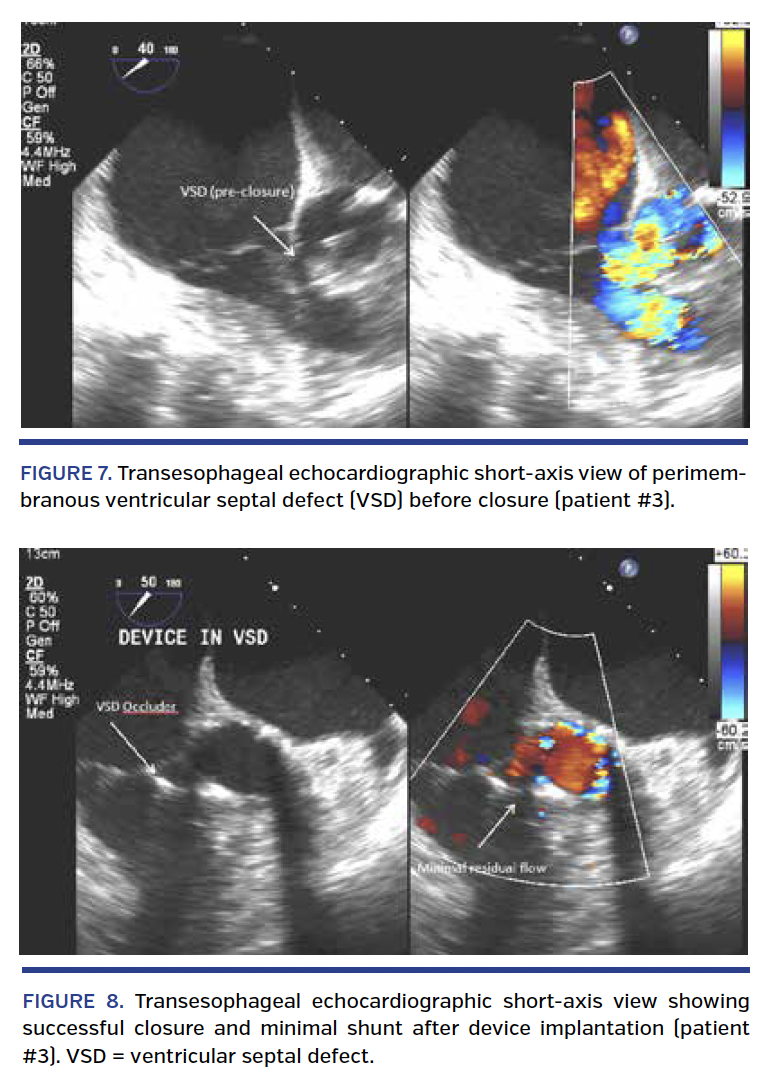

The patient was initially managed conservatively, but was subsequently readmitted with progressive heart failure symptoms 1 month after his TAVR procedure. Repeat TTE showed worsening LV systolic function with estimated LV ejection fraction of 35%-40%. TEE showed normally functioning TAVR with moderate-sized left to right shunt with flow from the LVOT to the RV consistent with a VSD (Figure 7; Video 8). Cardiac catheterization revealed a Qp/Qs of 1.6 with an estimated left-to-right shunt flow of 3.8 L/min. Pulmonary artery pressures were 45/13 mm Hg with a mean of 28 mm Hg, which were unchanged from his prior measurements. Given clinical decompensation and significant left-to-right shunt, it was decided to proceed with percutaneous closure of the VSD as previously reported.7

Closure of the VSD was performed under general anesthesia using TEE and angiographic guidance with a 10-mm diameter Amplatzer VSD occluder (St. Jude Medical, Inc) via an anterograde arteriovenous loop technique. Following deployment of the device, there was significant decrease in color flow across the VSD with residual mild shunt (Figure 8; Video 9). At his 1-month follow-up visit after VSD closure, the patient reported significant improvement in exertional dyspnea (NYHA class II). He was last seen in clinic 14 months after the VSD closure and has remained in NYHA class II clinically. Repeat TTE showed a mildly reduced LV ejection fraction of 45%, without any residual VSD.